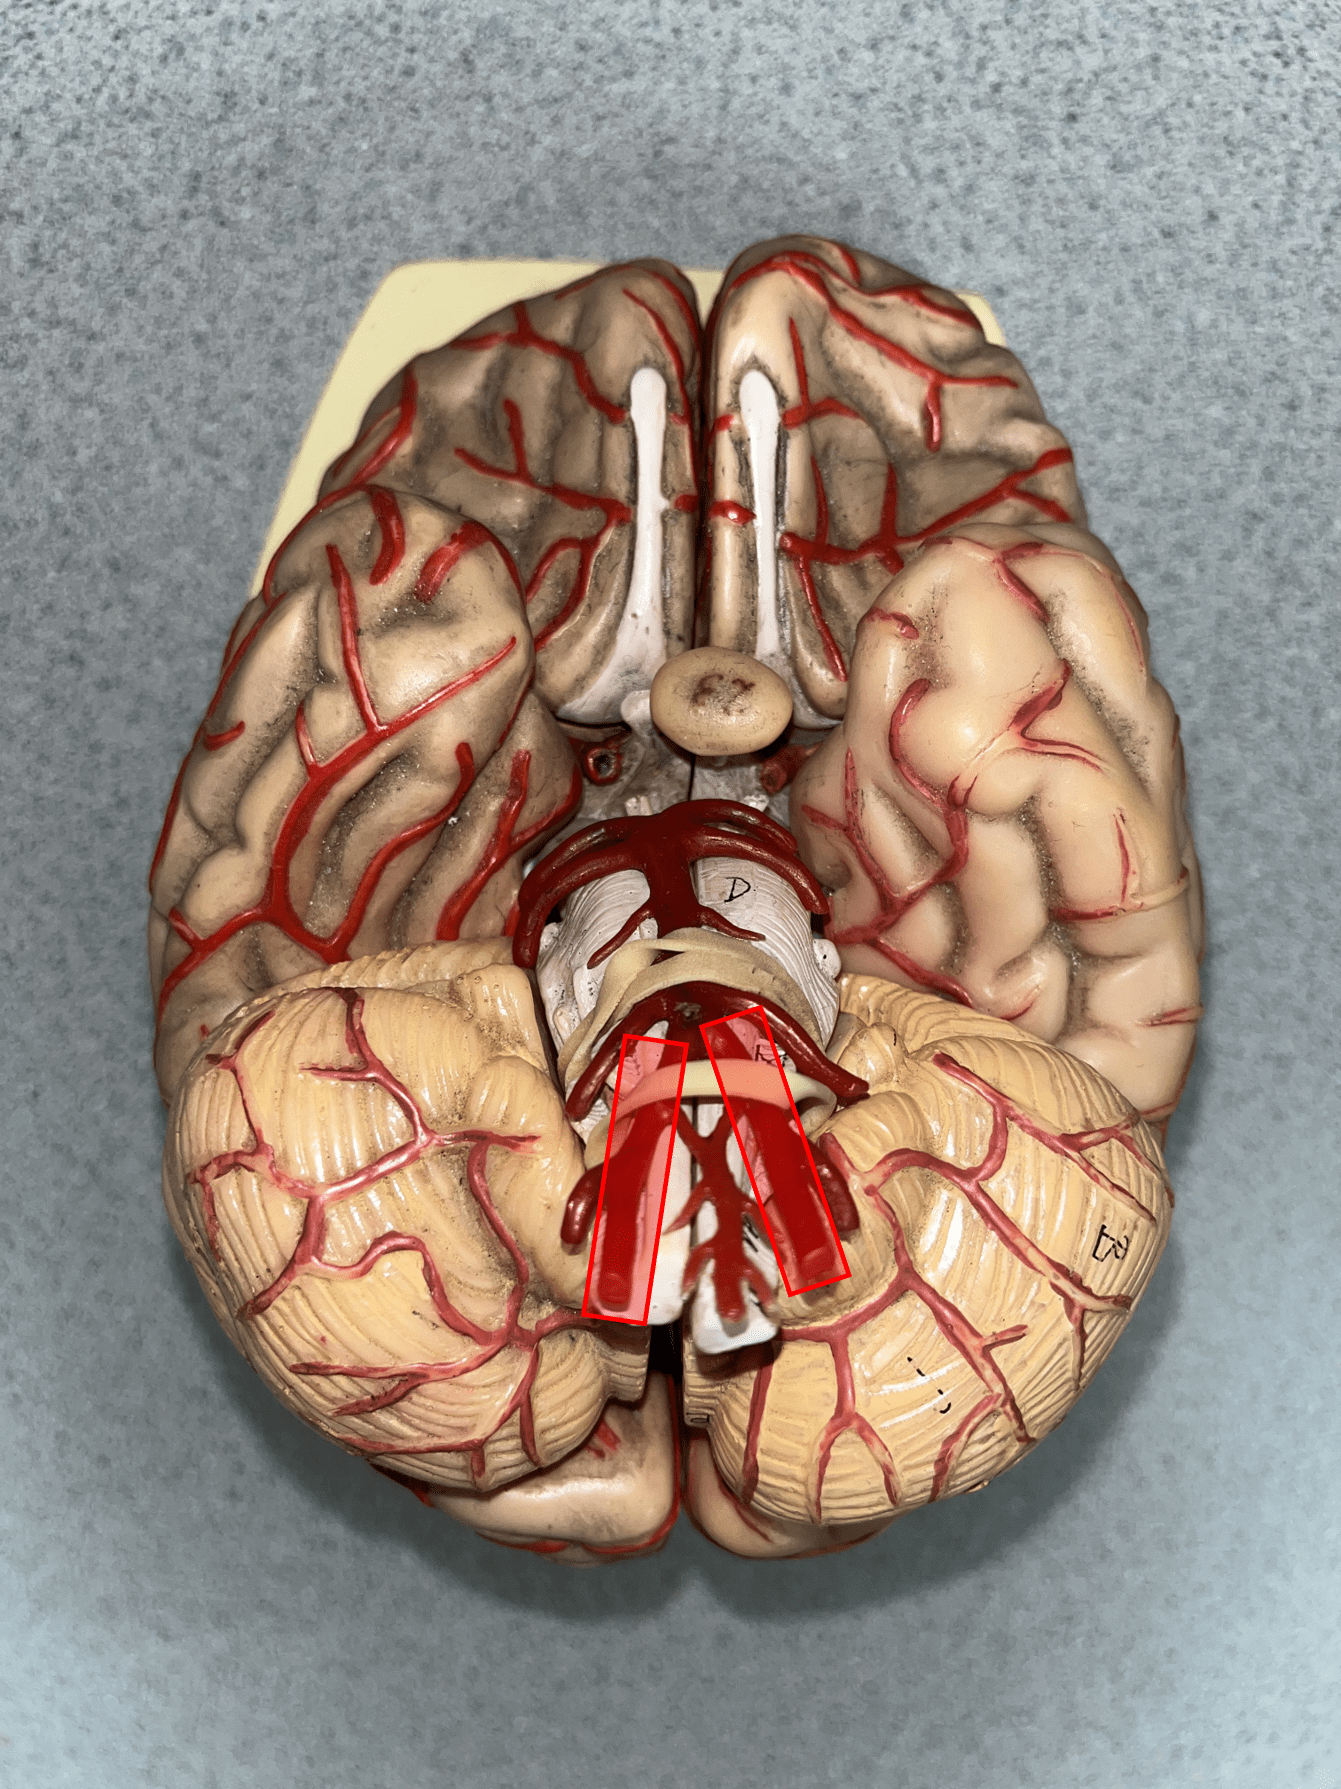

anterior cerebral artery

• An artery of the cerebral circulation.

• Originates from the internal carotid artery.

• Supplies the frontal and parietal lobes of the brain.

• Originates from the internal carotid artery.

• Supplies the frontal and parietal lobes of the brain.

28

New cards

anterior communicating artery

• An artery of the cerebral circulation (not shown).

• Connects the right and left anterior cerebral arteries.

• Connects the right and left anterior cerebral arteries.

29

New cards

posterior communicating artery

• An artery of the cerebral circulation (not shown).

• Connects the posterior cerebral and internal carotid arteries.

• Connects the posterior cerebral and internal carotid arteries.

30

New cards

posterior cerebral artery

• An artery of the cerebral circulation.

• Originates from the basilar artery.

• Supplies the temporal and occipital lobes, midbrain, and thalamus.

• Originates from the basilar artery.

• Supplies the temporal and occipital lobes, midbrain, and thalamus.

31

New cards

middle cerebral artery

• An artery of the cerebral circulation (not shown).

• Originates from the internal carotid arteries.

• Supplies the frontal, temporal, and parietal lobes.

• Originates from the internal carotid arteries.

• Supplies the frontal, temporal, and parietal lobes.

32

New cards

basilar artery

• An artery of the cerebral circulation.

• Originates from the convergence of the vertebral arteries.

• Supplies the cerebellum, pons, and inner ear through its branches.

• Originates from the convergence of the vertebral arteries.

• Supplies the cerebellum, pons, and inner ear through its branches.

33

New cards

superior sagittal sinus

• A vein of the cerebral circulation.

• Drains the superficial brain.

• Empties into the internal jugular vein.

• Drains the superficial brain.

• Empties into the internal jugular vein.

34

New cards

inferior sagittal sinus

• A vein of the cerebral circulation.

• Drains the deep brain.

• Empties into the internal jugular vein.

• Drains the deep brain.

• Empties into the internal jugular vein.

35